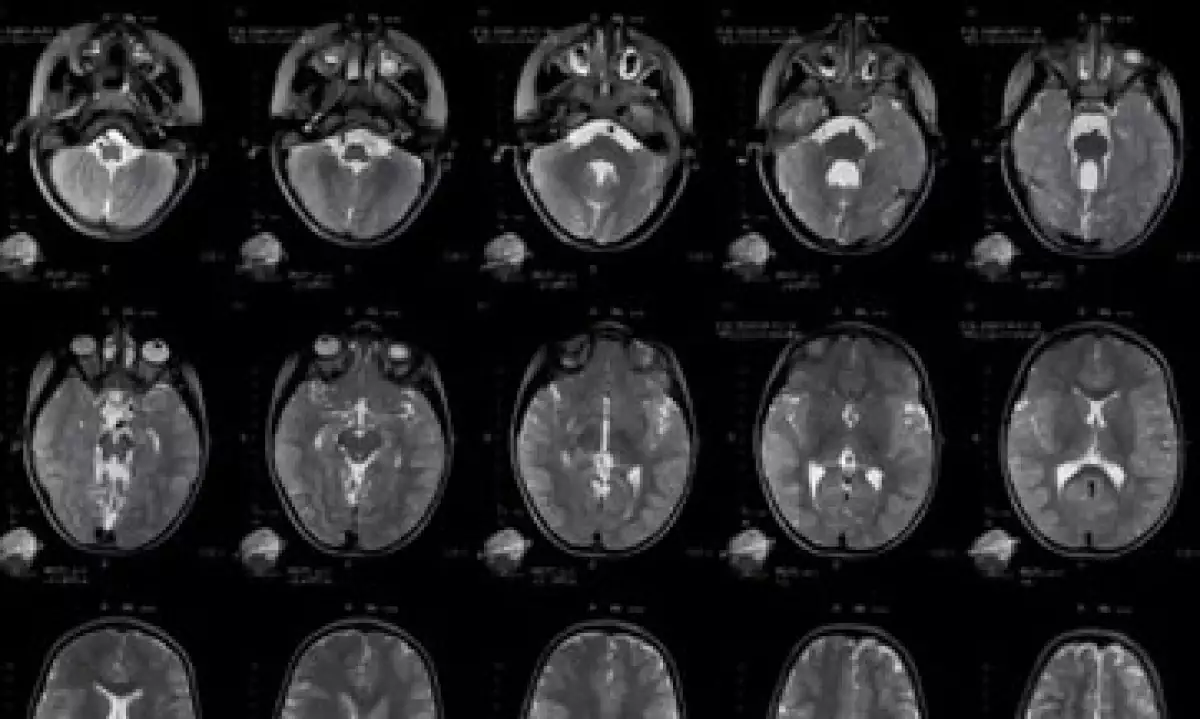

A los menores que se les identifican factores de riesgo que pudieran producir daño cerebral se les realizan estudios con técnicas de resonancia magnética para saber si existen alteraciones estructurales: para detectar riesgos funcionales se practican electroencefalogramas, mientras que para evaluar disfunciones conductuales se emplea la exploración neuropediátrica.